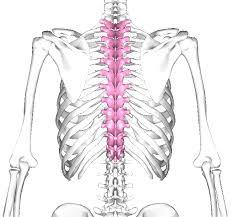

胸椎(きょうつい)

上から頸椎7個、胸椎12個、腰椎5個あります。

首や腰は回したり動かすことが多いですが、意外と胸椎を動かすことは少ないです。

本来は腰の何倍も回旋できる部位ですので、しっかり回したり動かしたりしましょう。